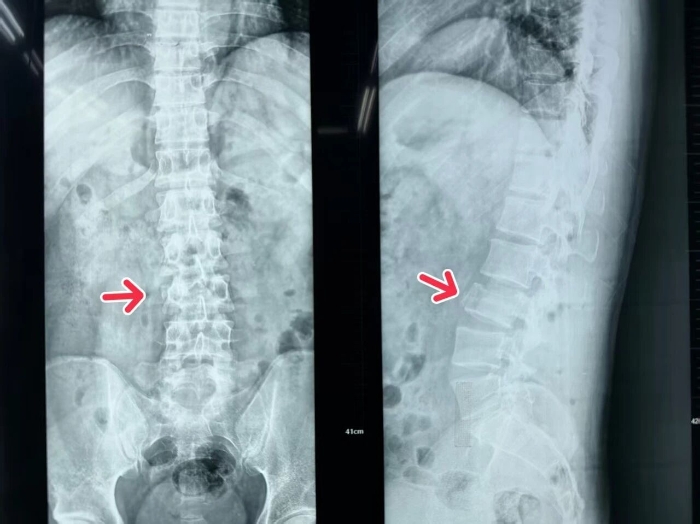

面对这位腰椎骨折伴神经损伤、随时可能因神经受压加重导致永久性残疾的患者,骨科姬传磊主任立即牵头组建急诊手术团队。影像科、麻醉科、手术室等多部门同步联动,在极短时间内完成腰椎CT、MRI等关键检查,明确损伤情况并排除手术禁忌,为后续手术争取了宝贵时间。

在姬主任的带领下,手术团队为患者施行了“腰椎骨折切开复位内固定+椎管减压术”。手术通过小切口精准操作,有效解除了骨折对脊髓神经的压迫,并实现了骨折椎体的复位与稳定固定。整个手术过程顺利,患者生命体征平稳,术后患者神经刺激症状显著缓解,安返病房。